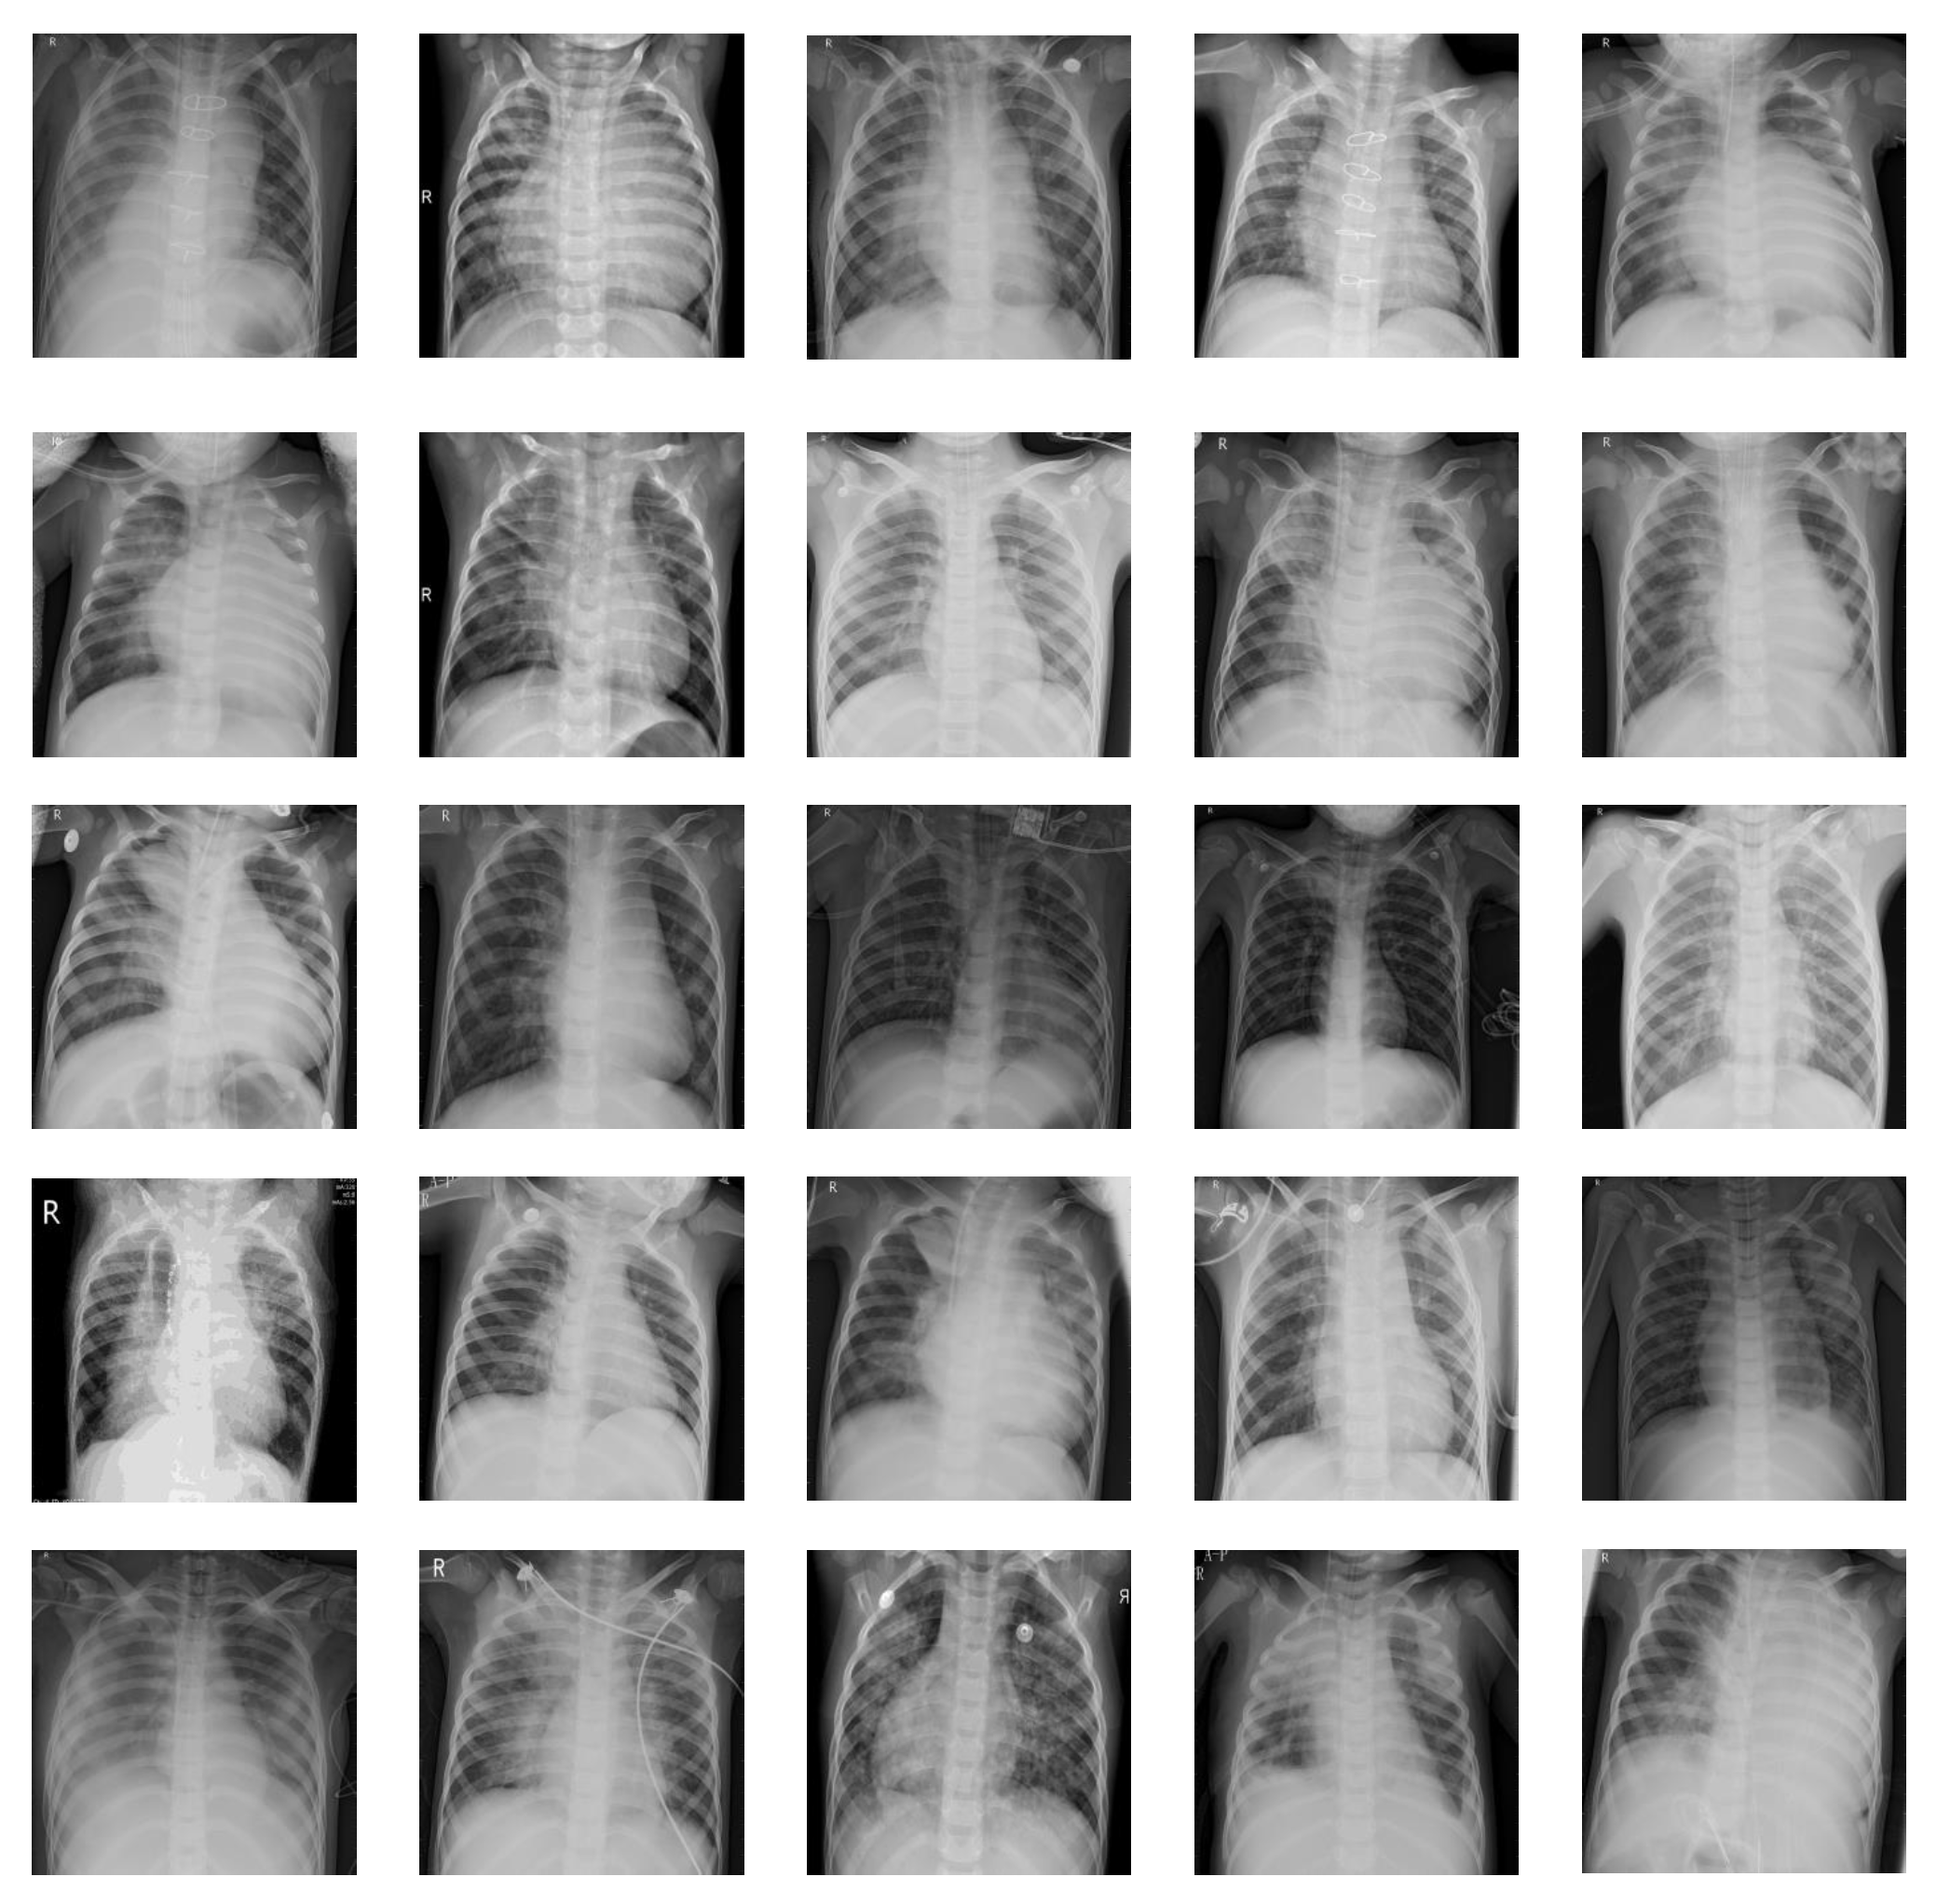

2.2. Step 1: Data Collection and Cleaning

2.2.1. Data Collection and Processing

| Pneumonia | 1575 X-ray images | Training set (80% randomly selected) | 1260 X-ray images |

| Testing set (20% randomly selected) | 315 X-ray images | ||

| Normal | 1575 X-ray images | Training set (80% randomly selected) | 1260 X-ray images |

| Testing set (20% randomly selected) | 315 X-ray images |